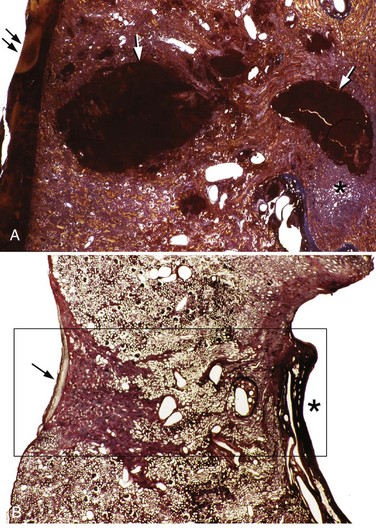

In porcine subjects, the preferred animal model for studying acute renal injury, SWL traumatizes vessels ranging in size from the glomerular and cortical capillaries and vasa recta, to the larger arcuate and intralobular vessels. The resulting hemorrhagic lesion generally extends from cortex to medulla and comprises torn blood vessels with platelet aggregation and red blood cells in the interstitial space (Figs. 48-25 and 48-26 on the Expert Consult website

). Renal tubules often contain blood cell casts, and the tubular cells may show ischemic changes. In the setting of a more severe injury, complete necrosis of the endothelium and vascular smooth muscle may result. A typical clinical dose of 2000 shockwaves with the Dornier HM3 lithotripter, operated at 24 kV with shockwaves delivered at 2 Hz produces a lesion measuring 5% to 6% of the functional renal volume (Fig. 48–28).

Figure 48–25 Light micrographs of an acute shockwave lithotripsy (SWL)-induced lesion at F2 (A) and subsequent chronic changes at a similar site 3 months after SWL treatment (B). Each pig kidney was treated with 2000 shockwaves at 24 kV by an unmodified Dornier HM3 lithotripter. The acute lesion is characterized by numerous sites of hemorrhage (arrows) that extend from an individual renal papilla (asterisk) to the outer cortex of the kidney. Note a subcapsular hematoma (double arrows, A). The tissue section in B is similar in location to that seen in A but is shown at 3 months after SWL. A rectangle outlines the site of F2. Within that region there is complete loss of the renal papilla (the asterisk indicates where it should be), and only scar tissue is found in the adjacent cortical tissue (arrow).

Figure 48–27 This series of light microscope panels depicts the injury seen in the cortex and medulla from an animal treated with 2000 shockwaves at 24 kV by an unmodified Dornier HM3 lithotripter. A and B illustrate extensive injury in both cortex and medulla. Within the cortex, disruption of arterial walls with hemorrhage (double arrows) is noted near sites of intraparenchymal bleeding (x). The first site of injury appears to occur in the renal medulla, where damage is noted to small vessels, which causes intraparenchymal hemorrhage (arrows) adjacent to damaged collecting ducts (arrowheads).